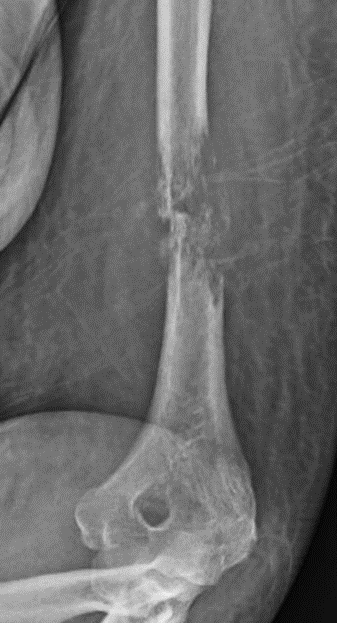

When cancer spreads to bones, it disrupts normal cellular activity and can result in increased bone formation (osteoblastic) or bone destruction (osteolytic) lesions. Both of these abnormalities can decrease the integrity of the bone, resulting in weakness and predisposing it to breaking. When bone breaks due to a metastatic lesion it is called a pathologic fracture (Image 1).

- Bone breaks, called pathologic fractures, can occur if the bone becomes so weak that it fails. These breaks can occur from low-force activities, such as pushing yourself up from a seated position or falling from a standing position. Typically, patients experience a sudden increase in pain and functional limitation when these breaks happen (Image 2).

X-ray is the simplest imaging study used to identify metastatic lesions. When a lesion is present, the bone will demonstrate the abnormal bone formation or destruction process. It can also show if the bone has broken or is close to breaking.